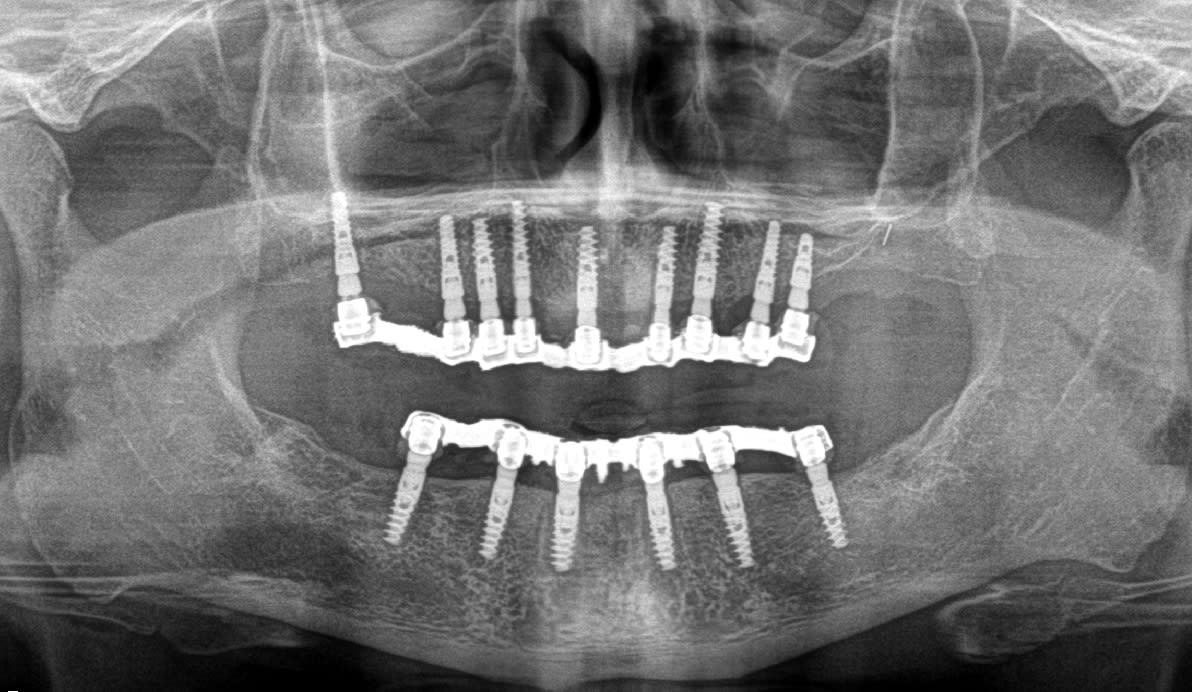

perso, je préfère ne pas perdre de temps (cf les repère chronologiques début-fin d'intervention) because time is money (et pour ce cas fait avec Alain, pas plus tard qu'hier, je ne suis pas à beaucoup plus de 10k€....)

Img 0001 axxxt4 - Eugenol

Img 0006 xdcmx3 - Eugenol

Img 0014 n2v53o - Eugenol

Img 0015 brdpvh - Eugenol

Img 0025 kzv3w5 - Eugenol

Img 0027 fwlgnt - Eugenol

Img 0037 n9s4o6 - Eugenol

Img 0038 yrxw5n - Eugenol

Img 0055 c9kovc - Eugenol

Img 0056 wzvlkq - Eugenol

Img 0063 vsmdns - Eugenol

Img 0072 irdf5w - Eugenol

je pense que certains copings se sont déplacés ou que tu les a mal positionnés avant le scellement...c'est en tout cas ce qu'il me semble voir avec ta pano (et voilà pourquoi je t'ai parlé du haut....)